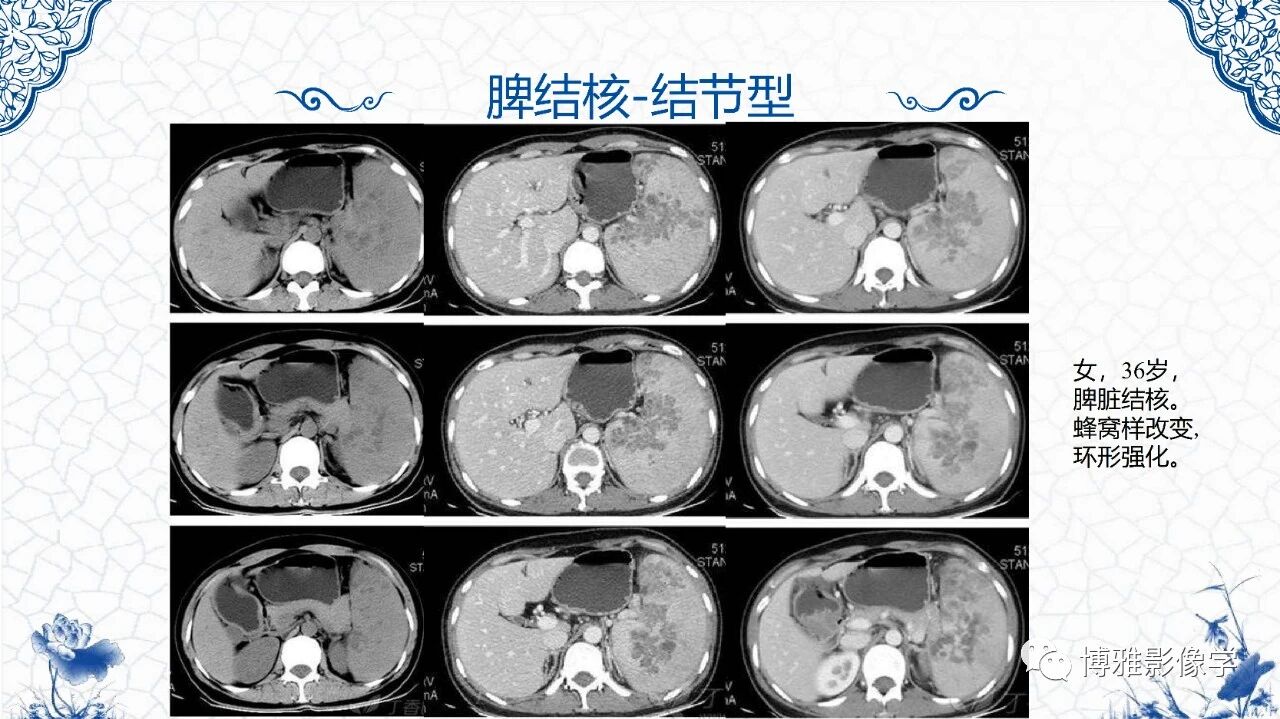

[腹盆] 脾脏非肿瘤影像诊断

脾脏非肿瘤影像诊断